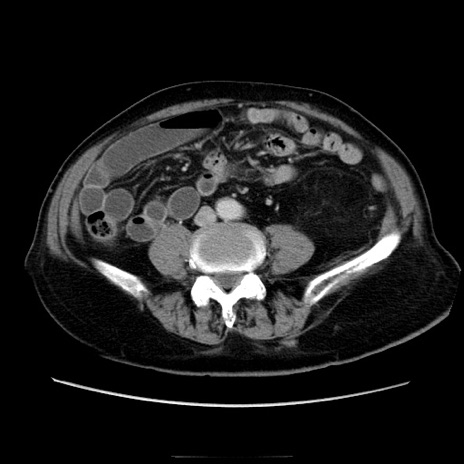

症例21(横断像)

【症例】70歳代男性

【主訴】腹痛

【現病歴】肝硬変・肝細胞癌にてかかりつけの方。約9時間前に食後より腹痛出現。症状が徐々に増悪し、嘔吐出現したため来院。

【既往歴】肝硬変、肝細胞癌(RFA、TACE後)

【身体所見】意識清明、表情苦悶様、BT 36℃、BP 129/78mmHg、P 88bpm、SpO2 97%(RA)、右上腹部から心窩部にかけて圧痛あり、反跳痛なし、筋性防御あり。

【データ】WBC 5800、CRP 0.16